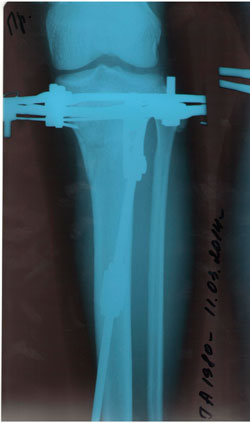

Дата операции 08.01.2014г.

Дата снятия аппаратов 15.04.2014г.

Срок лечения 98 дней.